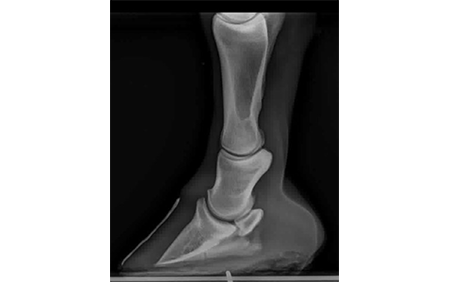

A Laminitic/Foundered Horse Foot X-Ray

Laminitis results from the disruption (constant, intermittent or short-term) of blood flow to the sensitive and insensitive laminae. These laminae structures within the foot secure the coffin bone (the wedge-shaped bone within the foot) to the hoof wall. Inflammation often permanently weakens the laminae and interferes with the wall/bone bond. In severe cases, the bone and the hoof wall can separate. In these situations, the coffin bone may rotate within the foot, be displaced downward ("sink") and eventually penetrate the sole. Laminitis can affect one or all feet, but it is most often seen in the front feet concurrently.

The terms "laminitis" and "founder" are used interchangeably. However, founder usually refers to a chronic (long-term) condition associated with rotation of the coffin bone, whereas acute laminitis refers to symptoms associated with a sudden initial attack, including pain and inflammation of the laminae.